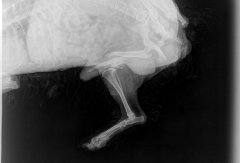

Aquí dejamos unos ejemplos reales:

Galería Radiografía digital